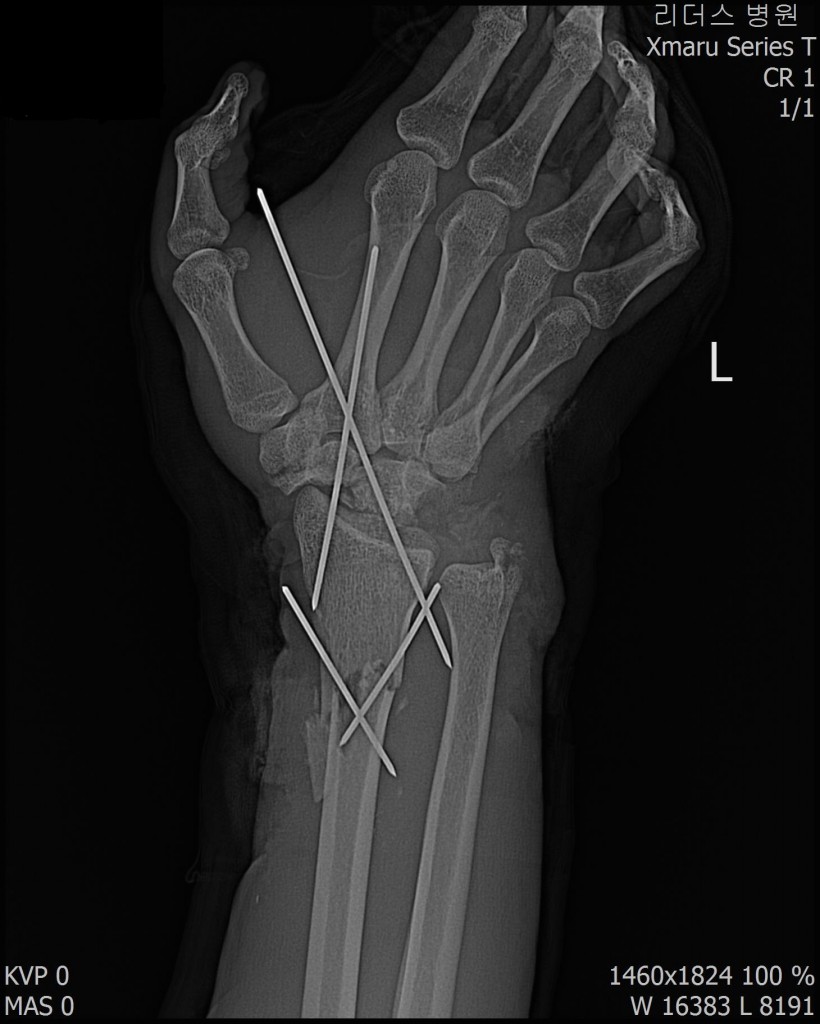

2017년 12월 23일 좌측 손목 절단 ( 치료 과정 모습)

20171223일 당시 ( 외국인 미 **)께서 좌측 손목 전달되어 본원 방문함.

2018.115일 현재 치료 중인 환자에 대하여 .....